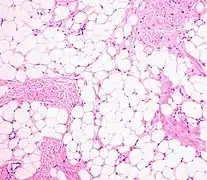

- Histopathology of a lipoma: The mass is composed of lobules of mature white adipose tissue divided by fibrous septa containing thin-walled capillary-sized vessels.[23]